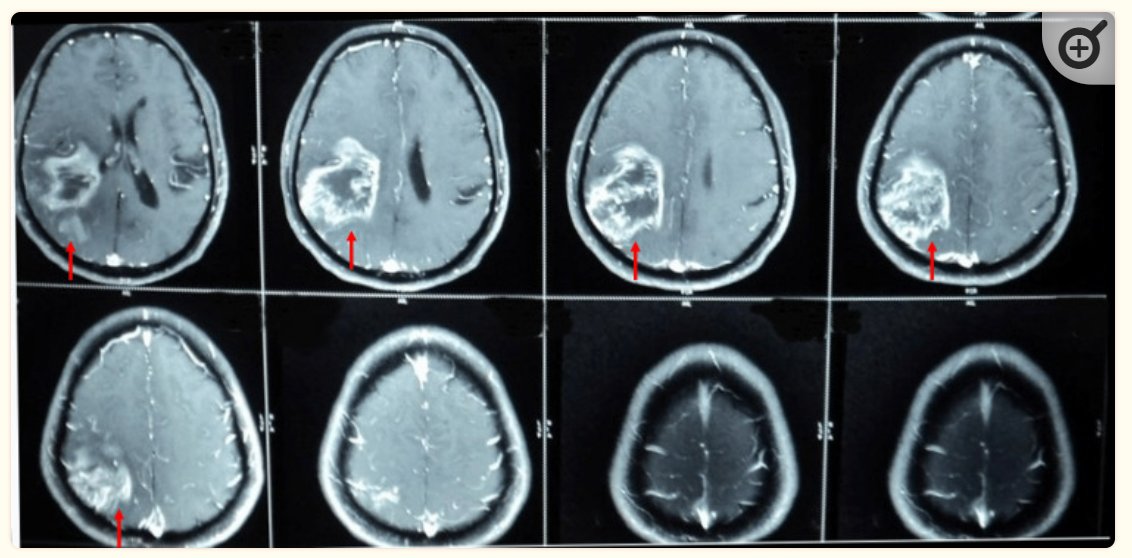

Very happy to share our new study, out now on Stroke AHA/ASA DWI lesion reversal is definitely a thing! It is a sign of successful MT and predicts good functional outcomes, no matter the age! Marco Pasi Charlotte Cordonnier Laurent Puy Martin Bretzner Gregoire Boulouis

Mohamad AbdalKader Thanh Nguyen 🇺🇦 "Contrast staining can be seen outside the infarcted tissue after EVT of AIS and is likely due to a reversible milder degree of BBB disruption. Although potentially benign, knowing its characteristics is important because it may mimic pathologic conditions."